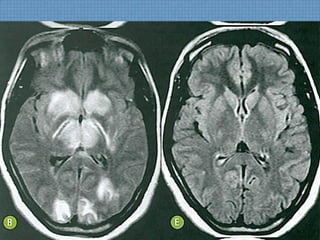

ACHADOS DE IMAGEM

• TC sem contraste:

– Hipoatenuação simétrica palidal;

• RM:

– Hipossinal em T1 palidal simétrico, podendo apresentar

realce periférico ou pontual pelo gadolíneo;

– Hiperssinal em T2/FLAIR em topografia medial de globos

pálidos  Isquemia ou Edema Vasogênico?

– Restrição à difusão indica irreversibilidade do dano neuronal;

– Cronicamente, lesões sequelares mostram-se com

hiperssinal em T2/FLAIR;

INTOXICAÇÃO POR CO

INTOXICAÇÃO SUICIDA-3H

• Hemorragia Palidal aguda bilateral;

DIFUSÃO

TC-ACHADOS SEQUELAS

INTUITO SUICIDA 3 ANOS ANTES